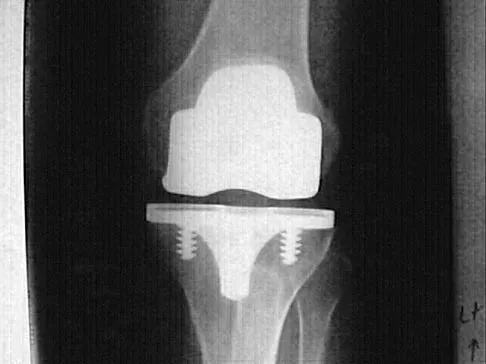

Question 16

A 15-year-old girl reports a 6-month history of activity-related knee pain and swelling. A radiograph, MRI scan, and biopsy specimen are shown in Figures 21a through 21c. What is the most likely diagnosis?

Explanation